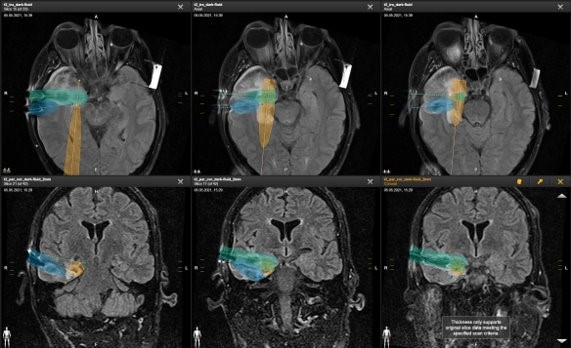

Visualase – MRT-geführte laserablationstechnologie

Der Patient ist und Narkose während des Eingriffs im Magnetresonanztomographen (MRT), der konstant Bilder und Temperaturmessung (auf das Grad Celsius genau) aus Herr Müllers Gehirn an die Neurochirurgen übermittelt. Außergewöhnlich: die Neurochirurgen operieren mit Computermaus und Touchscreen. Sie steuern mit Millimeterpräzession wie die LASER-Energie wirken soll. Als Besonderheit der OPs am ZFN nimmt auch der Neurologe Professor Dr. Christian Elger, Leiter des Kompetenzzentrums für Epilepsie, der die Voruntersuchungen überwacht und bewertet hatte, an der OP teil. Der Erfolg einer solch komplexen Hirn-Operation beruht im Besonderen auf Team Work und ruht auf den Schultern des zehnköpfigen OP-Teams! Nach der siebenstündigen Operation wacht Herr Müller aus der OP auf, er wird am Folgetag entlassen und ist seitdem frei von Krampfanfällen. Insbesondere für Eingriffe im Schläfenlappen muss die Gedächtnisleistung des Patienten besonders berücksichtigt werden. Durch den besonders schonenden Zugangsweg bei der Laserchirurgie lässt sich die Verletzung gedächtnisbildender Strukturen minimieren. Zusätzliche neurologische Ausfälle durch den Eingriff können daher im Vergleich zu klassischen Eingriffen in dieser Region weitgehend reduziert werden.

Nach mehreren Voruntersuchungen fand eine computergestützte und sogleich virtuelle Planung des funktionellen Hirn-Eingriffs von Frau Seidler satt. Die hierfür am ZFN eingesetzte Software des Münchner Unternehmens BrainLAB setzt international Maßstäbe für die zielgenaue und sichere Behandlung der Patienten. Bereits Tage vor dem eigentlichen Eingriff ist es so den funktionellen Neurochirurgen möglich die optimale Lage der THS Sonden virtuell festzulegen. Im OP setzen die funktionellen Chirurgen dann präzise diesen virtuellen Plan in die Tat um. Im Falle von Frau Seidler, die diesen Präzissionseingriff teilweise wach, aber ohne Schmerzen, erlebt, fließen Glücktränen als die erste Teststimulation das Gehirn zum ersten Mal mit schwachen Stromstößen wieder auf Trab bringt: ganz ohne Zittern und Verkrampfung gelingt ihr die Bewegung der Hand – eine Erfahrung, die Sie nach viele Jahren für fast unmöglich hielt. Nach Implantation der THS-Elektroden schließen die Chirurgen den sechsstündigen Eingriff mit dem Einbringen des mit einem Herzschrittmacher vergleichbaren mini-Computers ab.